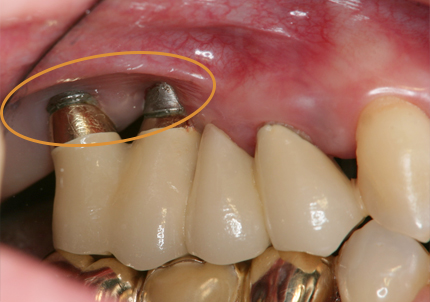

20.インプラント埋入

↑初期固定35N/cm(理想値)

21.インプラント埋入後(2021年1月27日)

22.上顎左側6番補綴物装着(2021年10月23日)